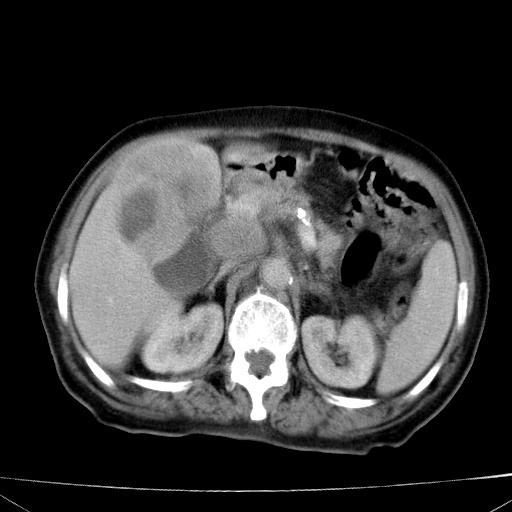

网站人气太旺!昨天的帖子就沉到海底,只好再发贴!ct18338:女 78岁,肝胆病变,已增强,再会诊!原帖链接:http://www.radida.com/bbs/forum.php?mod=viewthread&tid=50032

1)考虑胆囊癌侵犯肝脏并肝门区、腹膜后及右侧膈角后淋巴结转移。2)肝左叶近肝顶部囊肿。3)肝左叶肝内胆管结石。4)左肾近下极囊肿。